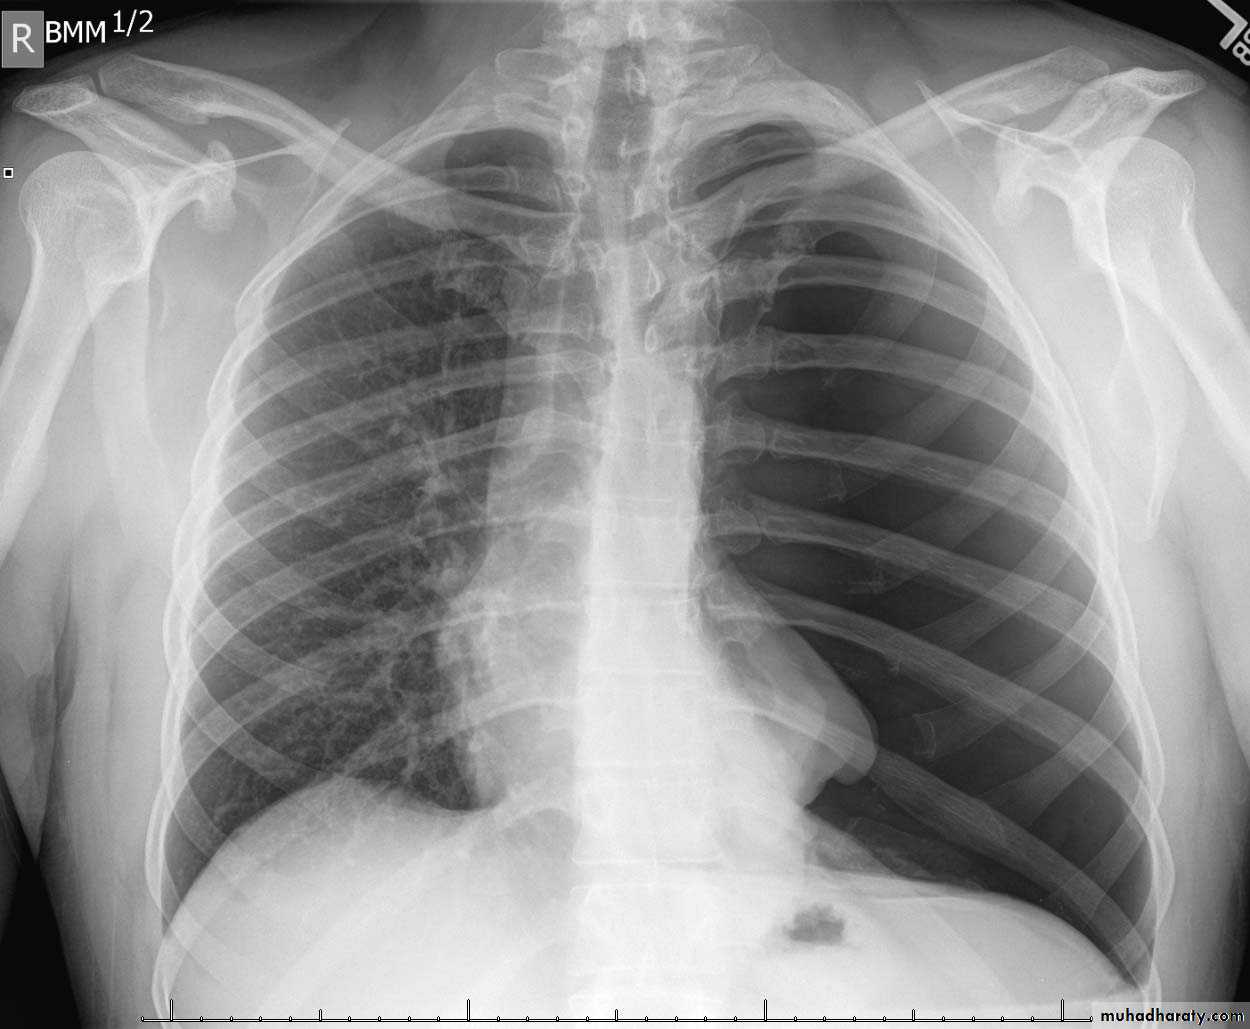

A tension pneumothorax

A tension pneumothorax occurs when intrapleural air accumulates progressively in such a way as to exert positive pressure on mediastinal and intrathoracic structures. It is a life threatening occurrence requiring rapid recognition and treatment is required if cardiorespiratory arrest is to be avoided.Radiographic features

A pneumothorax will have the same features as a run-of-the-mill pneumothorax with a number of additional features, helpful in identifying tension. These additional signs indicate over expansion of the hemithorax:

ipsilateral increased intercostal spaces

shift of the mediastinum to the contralateral side

depression of the hemidiaphragm

tension pneumothorax